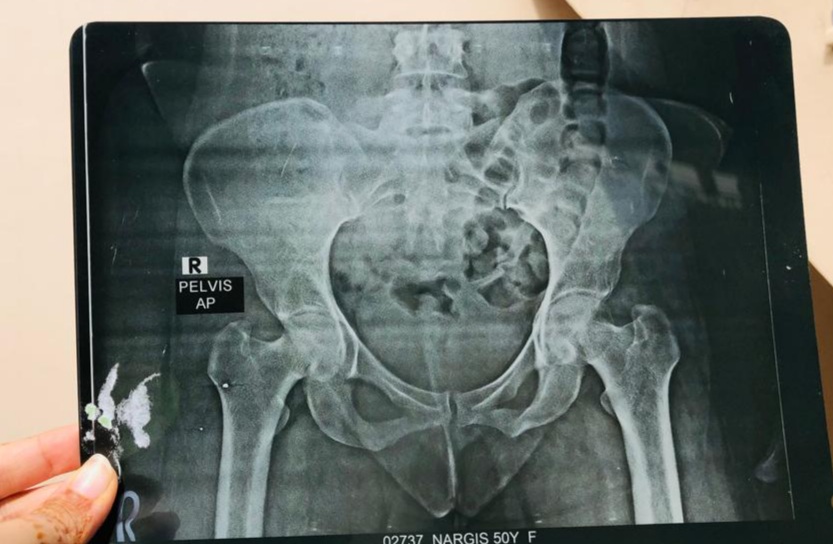

My aunt had remove her utress last year because she was facing problem of continously there is something happening in utress. A small ball with pain inside utress.i have an x Ray of this . Can u please guide me what is this?

My aunt had remove her utress last year because she was facing problem of continously bleeding.now there is something happening in utress. A small ball with pain inside utress.i have an x Ray of this . Can u please guide me what is this?

get her pelvic ultrasoud